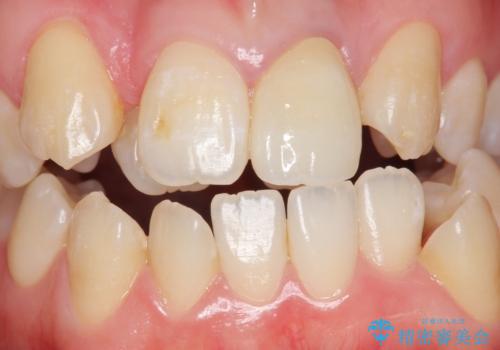

前歯が黒い セラミックで綺麗に 20代女性

- 前歯が黒くなってきたことを主訴に来院された患者様です。

精査したところ、う蝕により歯の内側から黒くなっていました。

根管治療後、セラミッククラウンによる補綴を行いました。